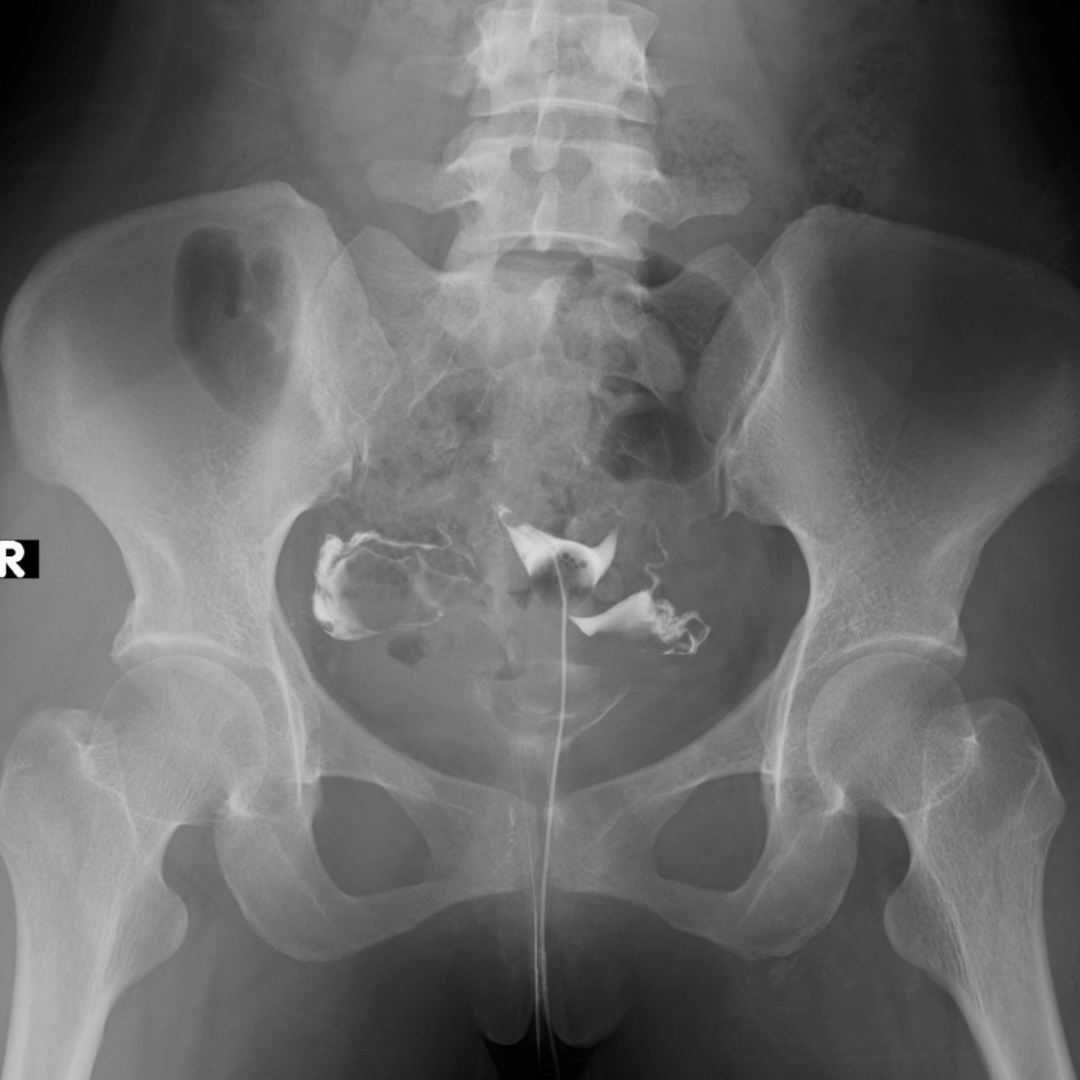

HSG adalah pemeriksaan dengan menggunakan sinar-X (rontgen) dan zat kontras untuk melihat kondisi rahim dan saluran tuba (saluran telur). Dengan pemeriksaan ini, dokter bisa mendeteksi kelainan di rahim maupun penyumbatan pada tuba falopi yang mungkin menjadi penyebab infertilitas.

Histerosalpingografi (HSG), yang juga dikenal dengan istilah “uterosalpingografi” atau “hidrotubasi”, adalah prosedur radiologi yang menggunakan zat pewarna kontras untuk mendapatkan gambaran rahim dan saluran telur melalui sinar-X.

Tujuannya: menilai bentuk rahim (apakah ada polip, miom, kelainan bentuk) serta memastikan apakah tuba falopi terbuka atau tersumbat.

- Zat kontras disuntikkan melalui selang tersebut sehingga aliran ke tuba falopi (jika terbuka) dapat terlihat pada sinar-X.

- Foto rontgen diambil dari berbagai sudut untuk melihat gambaran lengkap rahim dan saluran.